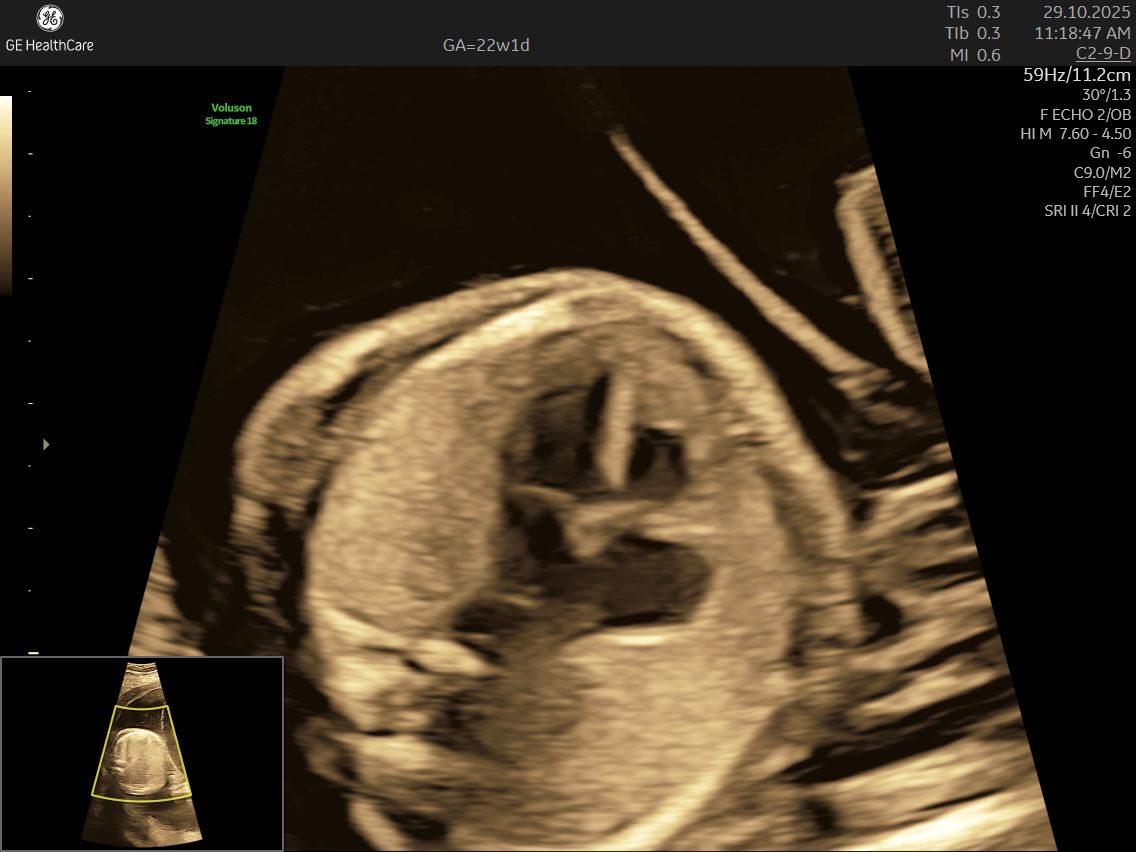

- Focus on the Heart: This scan is dedicated solely to assessing your baby’s heart—its structure, blood flow, and rhythm—offering a far deeper evaluation than standard ultrasounds.

- Specialized Equipment and Expertise: Performed with high-resolution machines and by specialist doctors, fetal echocardiography pinpoints tiny structural or functional abnormalities that conventional scans may miss—helping ensure early, accurate diagnosis and informed planning.

- Structural Defects: Such as septal defects (holes in the heart), valve abnormalities, and underdeveloped chambers.

- Its a specialized ultrasound done between 18–24 weeks of Gestational Age that evaluates the structure, function, and rhythm of a baby’s heart while still in the womb. This scan uses high-frequency sound waves to create detailed images of the fetal heart, aiding in the detection of congenital heart defects (CHDs) and other abnormalities.